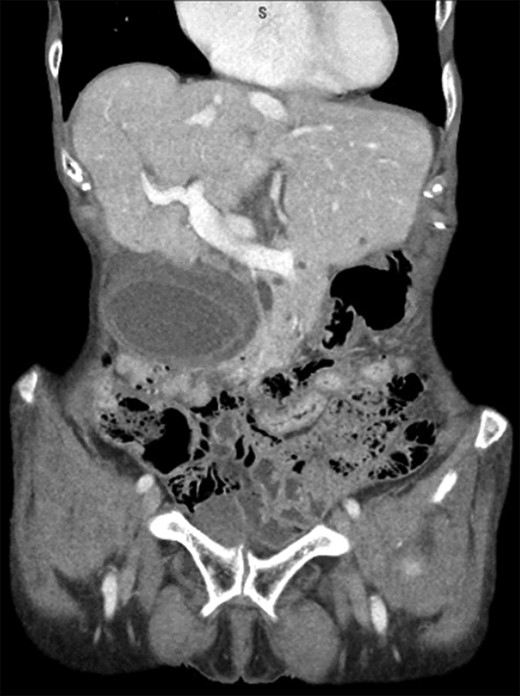

A 77-year-old female presented with acute right upper quadrant (RUQ) pain with associated nausea for 12 hours. Pain was described as dull and more severe after eating. The patient had prior episodes of this pain, occurring for the last several years. She admitted weight loss and denied any fevers, chills or vomiting. Medical history included hypothyroidism, hyperlipidemia, malabsorption problem for which she takes B12 and folic acid supplements. Surgical history included appendectomy. She denied any tobacco or alcohol use. Abdominal exam demonstrated a soft, non-distended abdomen with a palpable mass in the RUQ, RUQ tenderness to palpation without rebound or guarding. Lab values were significant for an elevated leukocytosis; chemistry and hepatic function panel within normal limits. CT scan demonstrated a distended hydropic appearing gallbladder with pericholecystic fluid and wall edema without evidence of gallstones (Fig. 1) and a common bile duct of 9 mm. Subsequent RUQ ultrasound revealed a dilated gallbladder with a thickened wall and a small amount of pericholecystic fluid, suggestive of acalculus cholecystitis. The patient was admitted, started on Cefepime and Flagyl, and scheduled for a laparoscopic cholecystectomy. Upon entering the abdomen, a large necrotic, gangrenous appearing gallbladder was noted (Fig. 2a–d). It had maneuvered itself over the top of the liver and completely necrosed its base. The gallbladder was extremely distended, encompassing much of the patient’s RUQ. The common bile duct was able to be identified. The gallbladder was not detorsed due to risk of toxin release into circulation as the gallbladder was gangrenous. Decompression of the gallbladder was not attempted due to concern for a possible malignancy. A 12 mm trocar was placed in the RLQ and a GIA stapler with Peristrips was used to completely transect the base of the gallbladder, including the cystic artery and duct. The gallbladder was placed in a large EndoCatch bag and the umbilical incision was extended to remove it from the abdomen. Hemostasis was achieved at the staple line and no other evidence of abnormalities were noted. The patient tolerated the procedure well. The patient had an uncomplicated postoperative course. Her postoperative hepatic function panel remained within normal limits. Histopathology was consistent with acute cholecystitis with gallbladder hemorrhage and necrosis (Fig. 3).

(a) Initial laparoscopic view of a severely distended and displaced gallbladder encompassing much of the RUQ. (b) Gallbladder base appears to have twisted upon itself and necrosed the base. (c) Transection across the gallbladder base with a GIA stapler. (d) Hemostasis achieved at transection size without damage to the liver.